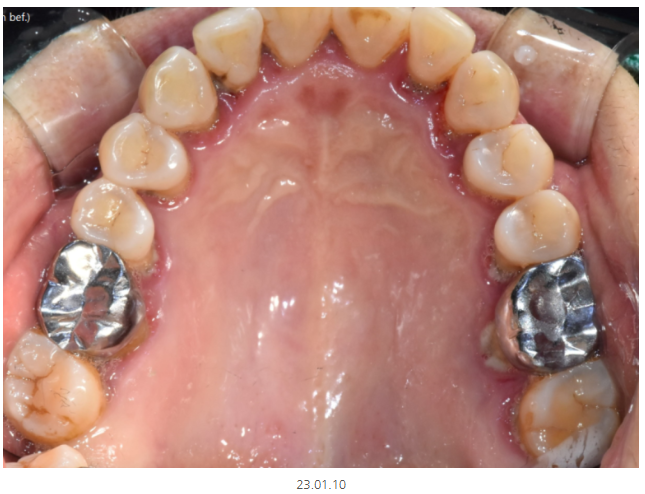

천호동 치과에서는 환자분들이 처음 오시면

꼭 지키는 원칙이 있습니다.

처음 상태를 그대로 카메라로 촬영합니다.

치아가 물리는 교합도 확인하는데요.

환자 1분당 최소 10분씩 걸리는 과정입니다.

엑스레이만으로도 진단이 가능하지만

그럼에도 시간투자를 하여 전체 사진을 찍어두는 이유

1️⃣확실하게 치료 전, 후 비교가 가능하다.

2️⃣환자분께 눈으로 확인시켜드릴 수 있다.

환자분들께 이해시켜드리기에는

눈으로 직접 보여드리는 수밖에 없더라고요~